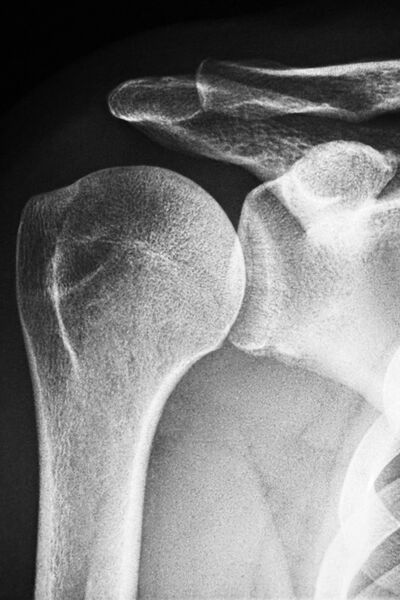

Das moderne Röntgen steht für eine exzellente Darstellung und Beurteilung von Erkrankungen z.B. im Bereich des Brustkorbs und Bauches oder auch bei Verletzungen des Skelettsystems.